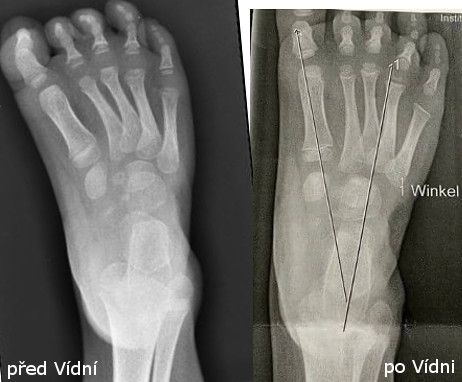

Po růstových spurtech, po 3. roce věku, nastala recidiva a nepomohlo ani cvičení dle Vojty, ani lázně. Zvýraznil se nášlap přes malíkovou hranu a dívka začala postupně chodit jen po špičce nohy.

Viditelně nedošlapuje na paty

Dorsiflexe v minusových hodnotách

Bylo potřeba začít úplně od začátku – znovu 5 sáder (konečně správně dle Ponseti metody) a opět udělat malý operační zákrok (tenotomie).